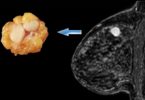

К первым относится маммография в нескольких проекциях. Возможность увеличения изображения позволяет выявить даже небольшие узелки. Крупные уплотнения могут обнаруживаться при проведении УЗИ молочной железы.